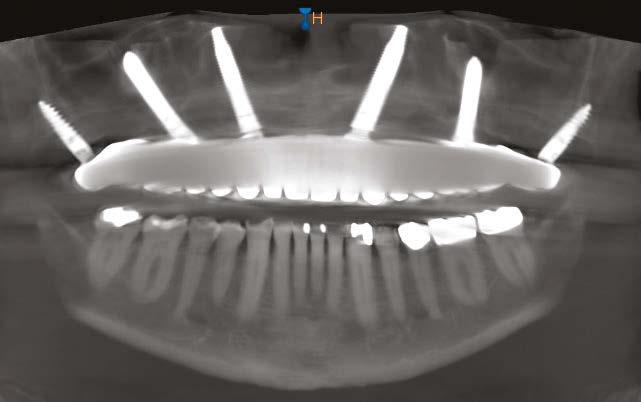

Due to the atrophic nature of the maxilla, treatment following the PATZi protocol was planned.6,17,20 CBCT evaluation revealed pterygomaxillary bone appropriate for pterygoid implants allowing for posterior arch support and cantilever elimination. The zygomas were of adequate height and width to accommodate multiple zygomatic implant fixtures bilaterally. PLACATE guidelines were used to evaluate the patient for potential treatment with transnasal implants. With Simmen 3 nasolacrimal canal classification, ≥ 3 mm of prelacrimal bone, ≥2 mm subnasal bone, and ≤ 25 mm to the Z-point, the patient satisfied all PLACATE parameters. Accordingly, a treatment plan of bilateral pterygoid, single zygomatic, and transnasal implants was agreed upon.

Following the induction of general anesthesia, extraoral and intraoral local anesthesia was applied. To avoid exposing the large subantral bony defects, mini-flaps were elevated at the pterygoid landing areas to expose the hamular notch. The pterygoid fossa was identified via probing, and pterygoid implant placement ensued. Following the PATZi protocol, bilateral pterygoid implants were placed first and both achieved insertion torque between 45+ Ncm.

Following PATZi, anterior support was sought next. As such, the nasal mucosa was elevated to expose the floor of the nasal cavity and the bone of the inferior conchae. A pair of 25 mm transnasal implants were placed, and each achieved high insertion torque of 45+ Ncm (Figures 9-11). Continuing with the PATZi protocol and treatment plan, 42.5 mm long zygomatic implants were placed in both zygomas. The zygomatic implants were placed using an extrasinus approach and both achieved insertion torque of 45+Ncm. Buccal fat pedicles were advanced bilaterally to cover extrasinus portions of the zygomatic implants, and flap closure was achieved with 4-0 chromic gut suture. The patient was immediately temporized with a screw-retained transitional bridge (Figure 12), and a final zirconia restoration was delivered after 8 months of healing (Figure 13).

Figure 10 (left): CBCT slice (coronal view) of transnasal dental implants engaging the Z-point. Figure 11 (middle): CBCT slice (sagittal view) of transnasal dental implant engaging prelacrimal bone ventral to the nasolacrimal duct. Figure 12 (right): 3-dimensional CBCT rendering of patient treated with transnasal, zygomatic, and pterygoid dental implants via the PATZi protocol